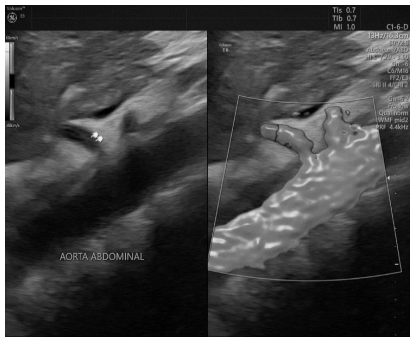

Em relação ao doppler, assinale a alternativa correta.

Qual estrutura está apontada na imagem a seguir e quais vasos se ramificam diretamente dela em condições habituais?